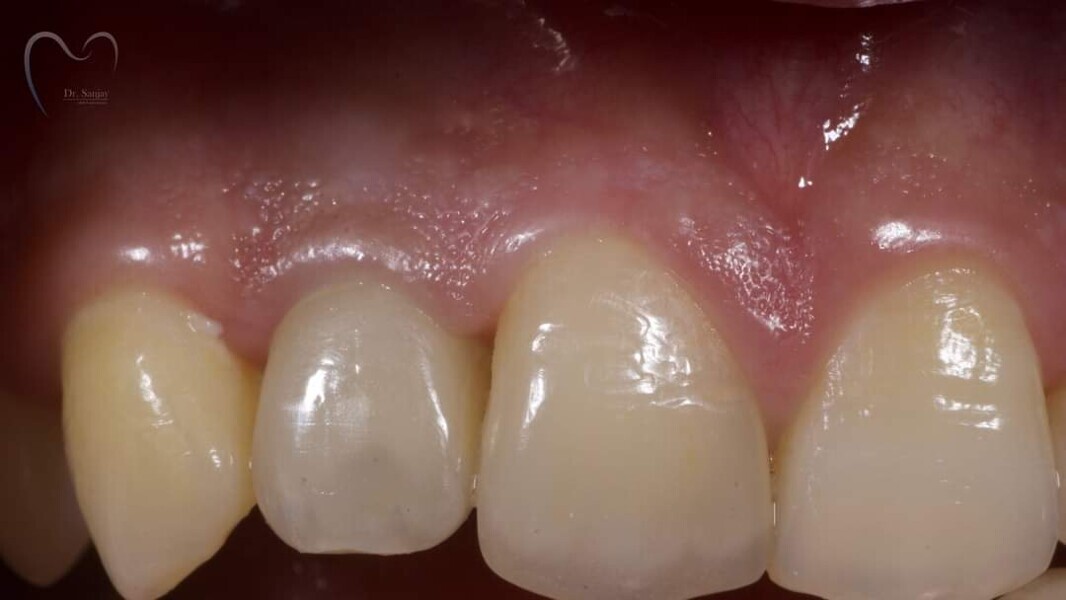

Esthetic Rehabilitation of Maxillary Anterior Teeth: Dr Sanjay Sah